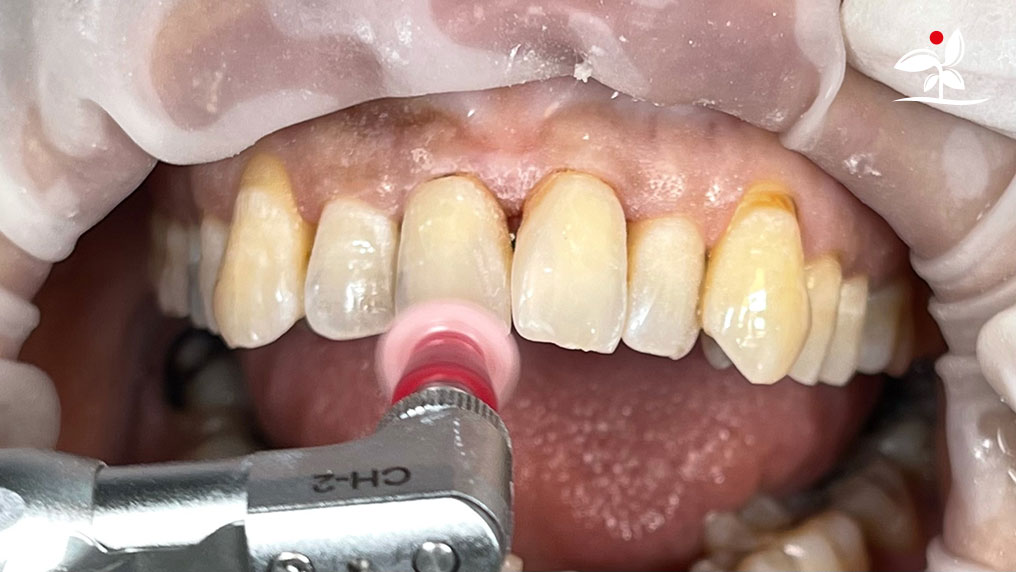

Restoration of Class IV Lesions using Naturomimetic Layering Technique (NLT) and Bioactive Restorative Materials

With the growing awareness about the health, function and aesthetic benefits of preserving natural tooth structure, patients are now globally demanding for aesthetic dentistry with minimally invasive procedures that has a low biological cost. This public demand has encouraged logical clinicians to adopt to the minimally invasive cosmetic dentistry (MiCD) concept and its treatment protocol [1] in their practice. The author has been using MiCD concept and its treatment protocols since 2017, which

include the methods of treatment that are simple, fast, predictable and healthy. In aesthetic restoration, the tooth color restorative materials placement technique is one of the most challenging, confusing and frustrating areas to learn owing to the multiple techniques that have been proposed by many clinicians and replicating such techniques in practice is not always as easy as they are marketed in dentistry. Natural teeth are complex in structure and hard to simulate due distribution of colors through enamel and dentin [2]. Aesthetic restoration strategies should follow proper understanding of defects, right selection of restorative materials along with their proper application, finishing, texturing and polishing [2].